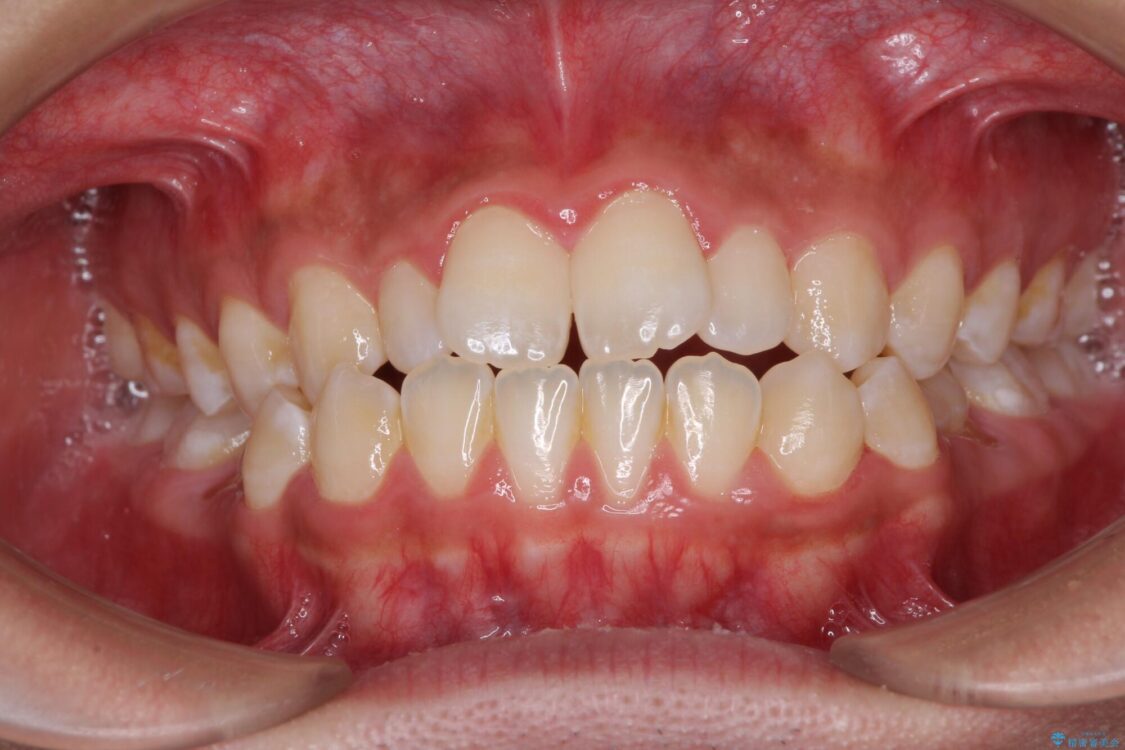

治療後

• 口元の突出感を改善 受け口傾向の咬み合わせの抜歯矯正 治療後画像